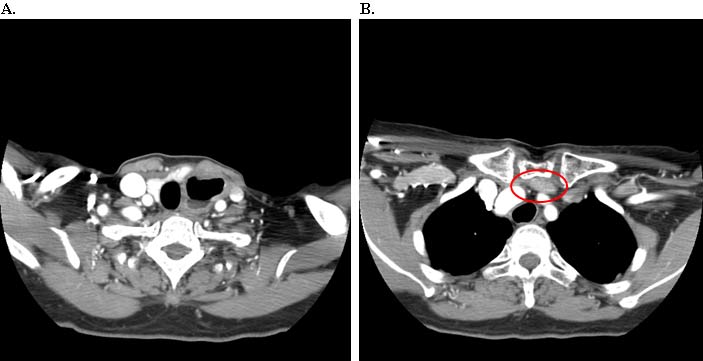

A 67 year old patient with a history of transhiatal esophagectomy (THE) and sub-sternal gastric pull-up ten years prior, at another institution, for early stage esophageal cancer presented with progressive dysphagia to solids. An initial esophagogastroduodenoscopy (EGD) found a large retained food bolus as well as tortuosity and dilatation of the cervical esophagus proximal to the esophagogastric anastomosis. No evidence of intrinsic anastomotic stricture or fibrosis was noted, but there was extrinsic compression. A barium esophagogram revealed significant extrinsic compression of the upper esophagus in the area of the anastomosis at the left clavicular head, with associated narrowing of the lumen and minimal transit of oral contrast (Figure 1). A computed tomography scan of the neck confirmed the sub-sternal location of the gastric pull-up within the anterior mediastinum, and revealed dilatation of the esophagus proximal to the anastomosis, with no associated masses or disease recurrence (Figure 2). The left sternoclavicular joint (SCJ) appeared to be compressing the conduit and was the point of obstruction.

Intraoperatively, the gastric conduit was noted to be intimately compressed by the left SCJ (Figure 3A). The insertion of the sternocleidomastoid and other strap muscles were divided using electrocautery and the conduit was carefully bluntly dissected off the posterior sternum and left SCJ. The manubrial and clavicular segments of the SCJ were then resected, revealing the conduit underneath in good condition (Figure 3B). Care was taken to preserve the left internal mammary artery. Intraoperative EGD confirmed easy passage of the scope through the cervical anastomosis and into the gastric conduit with reduced extrinsic compression. Saline irrigation into the field and air insufflation of the conduit was used to confirm conduit integrity. A Savary-Gilliard guidewire was endoscopically passed and the anastomosis was carefully dilated using 42, 48, and 54 French (Fr) Savary-Gilliard bougie dilators (Cook Medical, Bloomington, IN) with minimal resistance. After removal of the guidewire, a 52 Fr Maloney dilator (Medovations, Milwaukee, WI) was also passed through the conduit without difficulty.